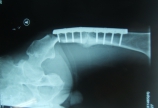

【下肢骨折】内固定周围再骨折

病情概述: 病例男性,56岁股骨干骨折术后5年愈合不佳,行走是摔伤致钢板近端再次骨折。在本次骨折前大腿行走无疼痛。1现在内固定选择长锁定板或髓内针?2以前愈合不佳的骨折端做不做植骨处理。 [详情]